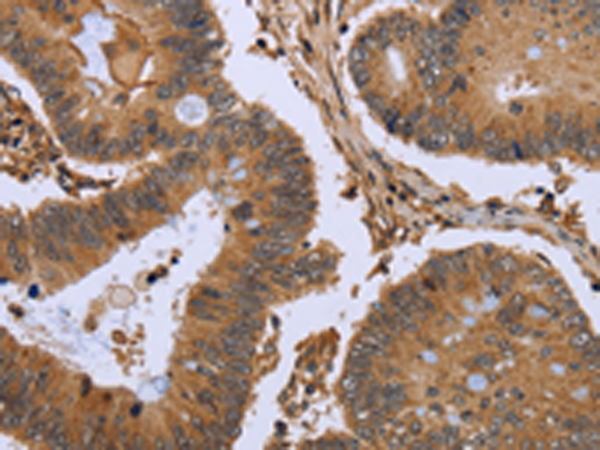

分类: 科研抗体货号: P08304别名: D5D; TU12; FADS6; FADSD5; LLCDL1应用: WB,IHC反应种属: Human, Mouse, Rat